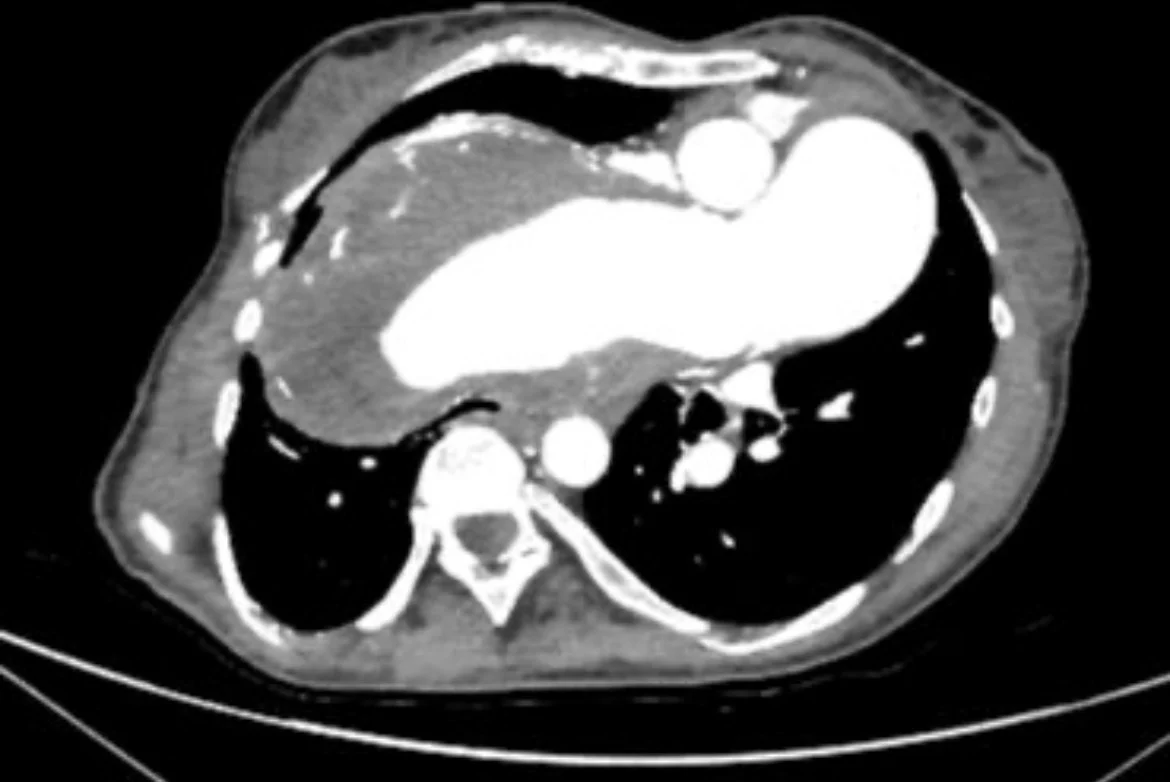

“Jovana Tumanov, Jelena Cavić, and I (with special help from Jelica Vukmirović) have another complex case of in situ pulmonary arterial thrombosis due to longstanding Eisenmenger physiology presenting with hemoptysis, which we have submitted to Radiopaedia.

At first sight, the CT appearances mimic chronic thromboembolic pulmonary hypertension (СТЕРН), which also increases pulmonary vascular resistance, causing progressive right heart strain; recognition of the VSD seals the diagnosis.